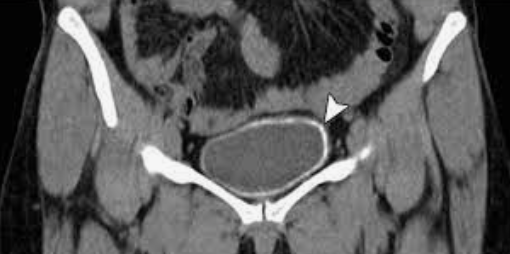

Cystogram in the setting of traumatic injury

Intraperitoneal bladder rupture, requiring surgery Note: Contrast is spreading "freely" in the peritoneal cavity, including left parabolic gutter (yellow arrow).

How can you differentiate extraperitoneal and intraperitoneal bladder rupture?

Extraperitoneal rupture (much more common) results in leaked contrast accumulating near the bladder (e.g. molar tooth sign) Intraperitoneal rupture (more rare) results in contrast freely flowing in the peritoneal cavity (look for it outlining bowel loops)